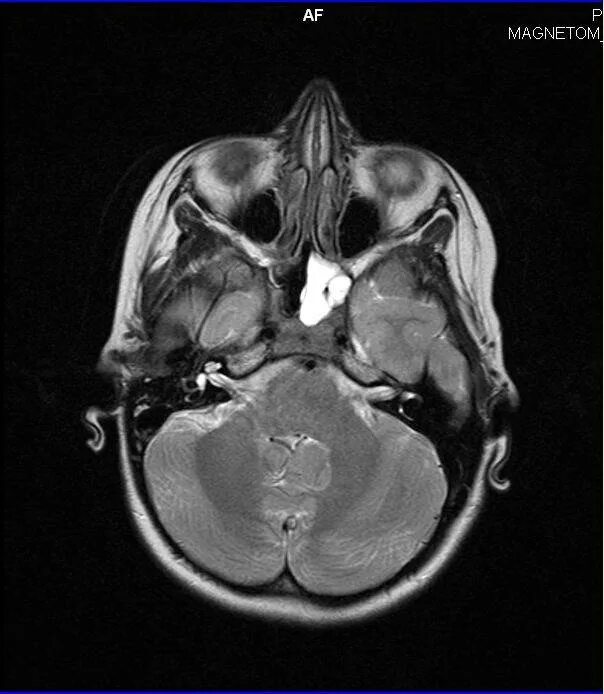

Сфеноидит симптомы